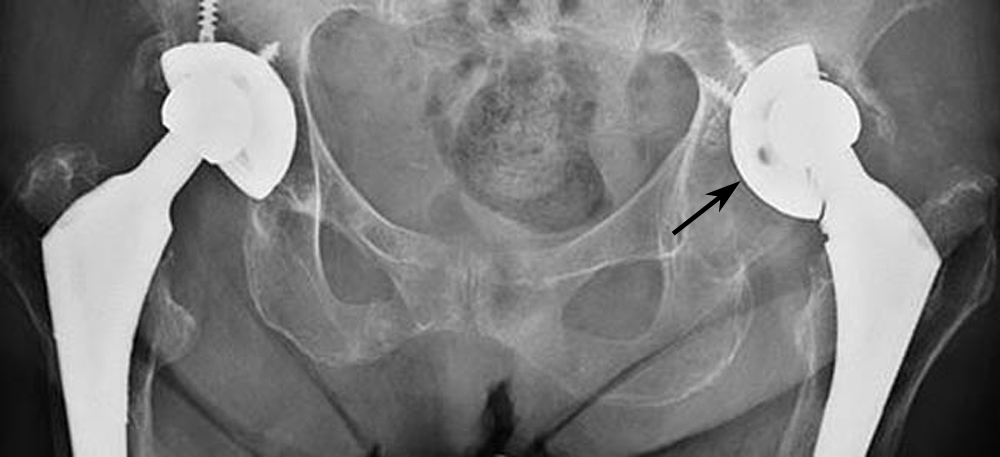

X-ray of loose acetabular cup

The acetabular cup on the left (arrow) has loosened from the underlying bone. As a result, the femoral head (ball) is no longer centered in the cup.